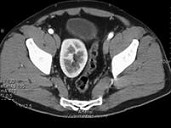

- 单项选择题男,27岁, 根据所示图像,最可能的诊断是 ( )

A、盆腔肾

B、腰段肾

C、胸内肾

D、肾下垂

E、游走肾